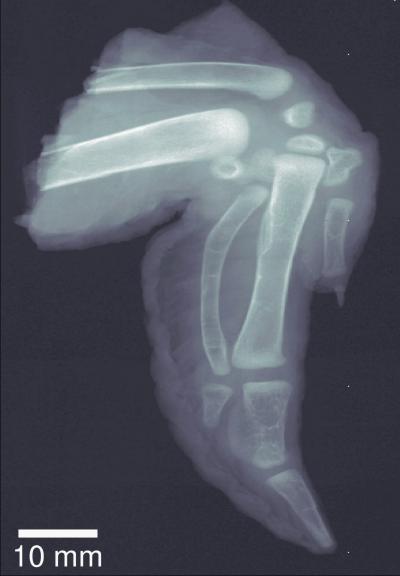

Unlike traditional x-ray images, which show a simple absorption contrast, dark-field images capture the scattering of the radiation within the material itself, exposing subtle inner changes in bone, soft tissue, or alloys. The overall clarity of the images is striking. The improved sensitivity in measuring bone density and hairline fractures could help diagnose the onset of osteoporosis. Because cancer or plaque cells scatter radiation slightly differently than normal cells, dark-field x-ray images can also be used to explore soft tissue, providing safer early diagnosis of breast cancer or the plaques associated with Alzheimer’s disease.

Security screening equipment equipped with dark-field image capability could better identify explosives, whose micro-crystalline structures strongly scatter x-ray radiation. And because x-rays penetrate a material without damaging it, dark-field images could help reveal scattering-producing micro-cracks and corrosion in structures such as airplane wings or the hulls of boats.